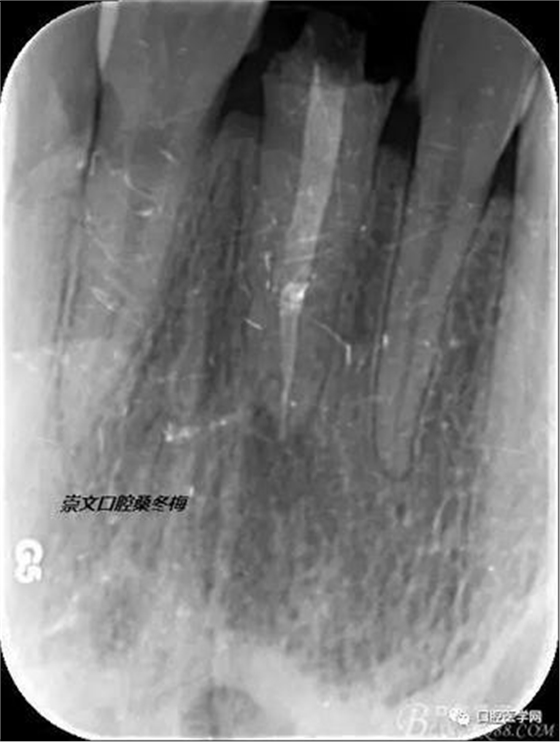

牙冠延長(zhǎng)術(shù)后6周復(fù)診牙齦齦緣形態(tài)恢復(fù)良好,齦乳頭有些欠缺,患者著急永久修復(fù)。

比色

纖維樁+樹(shù)脂核

樁道長(zhǎng)14mm

備牙

戴牙